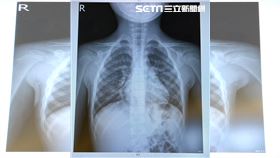

黴漿菌難診斷!兒科醫揭1症狀懷疑線索

中國黴漿菌等呼吸道疾病激升,台灣也出現病例。小兒科醫...